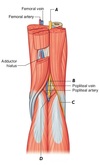

Name nerves A and B

A - Common fibular nerve

B - Tibial nerve

Name structures A to D

(N.B - D is posterior to the Calcaneal tendon)

A - Medial head of the gastrocnemius

B - Plantaris

C - Lateral head of the gastrocnemius

D - Tendon of plantaris